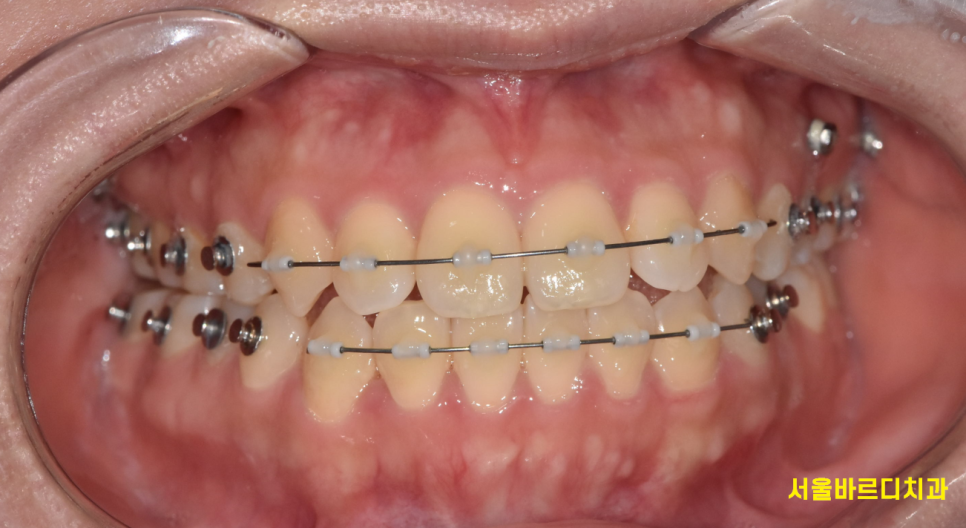

치아교정 장치는 크게 고정식 교정 장치와 가철식 교정 장치로 나눌 수 있습니다.

250304 철사형 장치

철사를 붙여서 진행할지~

꼈다 뺐다하는 투명교정으로 진행할지 결정해주어야하는거죠